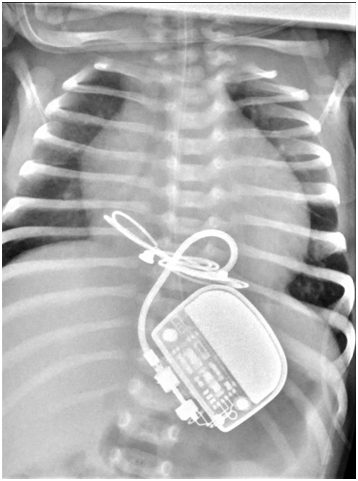

Initial full blood count showed mild thrombocytopenia of 101,000/mm3. Platelet count decreased gradually to the lowest value of 37,000/mm3 at the age of one week. Then, the number gradually improved back to normal at 314,000/mm3 without intervention at the age of 2weeks. Cranial ultrasonography revealed bilateral linear echogenic streaks at the basal ganglia, suggestive of lenticulo striate vasculopathy (Figure 3). Abdominal ultrasonography showed borderline hepatosplenomegaly but no ascites. Blood chemistry tests including urea, electrolytes, creatinine; liver function tests; and bone profile were all within normal limits. The STORCH profile was negative. At the age of 5 days, atropine injection was administered without improvement of heart rate, and furosemide was commenced in view of development of signs of heart failure clinically and by echo assessment. In the next week, there was progressive increase in respiratory distress with further enlargement of cardiac chambers, and the decision for cardiac pacing was planned. Permanent Medtronic bipolar epicardial pacing leads were implanted on the right ventricle. Pacing leads were connected to St. Jude Microny 2 pacemaker pulse generator placed in a pocket created below the rectus sheath in the left upper abdominal quadrant (Figure 4). Parameters were checked and paced at the 100bpm VVIR mode. The infant was clinically stable after pacing with improvement of respiratory and cardiac function. Repeated ECG showed stable heart rhythm and rate at 100bpm (Figure 5). She was gradually weaned to room air 5days after surgery and discharged home one week later with stable hemodynamic status. Upon follow-up in the outpatient clinic till the age of one year, she was developmentally normal and gaining weight and had normal cardiac functions.

Figure 4 Chest radiogram shows permanent Medtronic bipolar epicardial pacing leads implanted on the right ventricle with pacemaker pulse generator placed below the left rectus sheath.